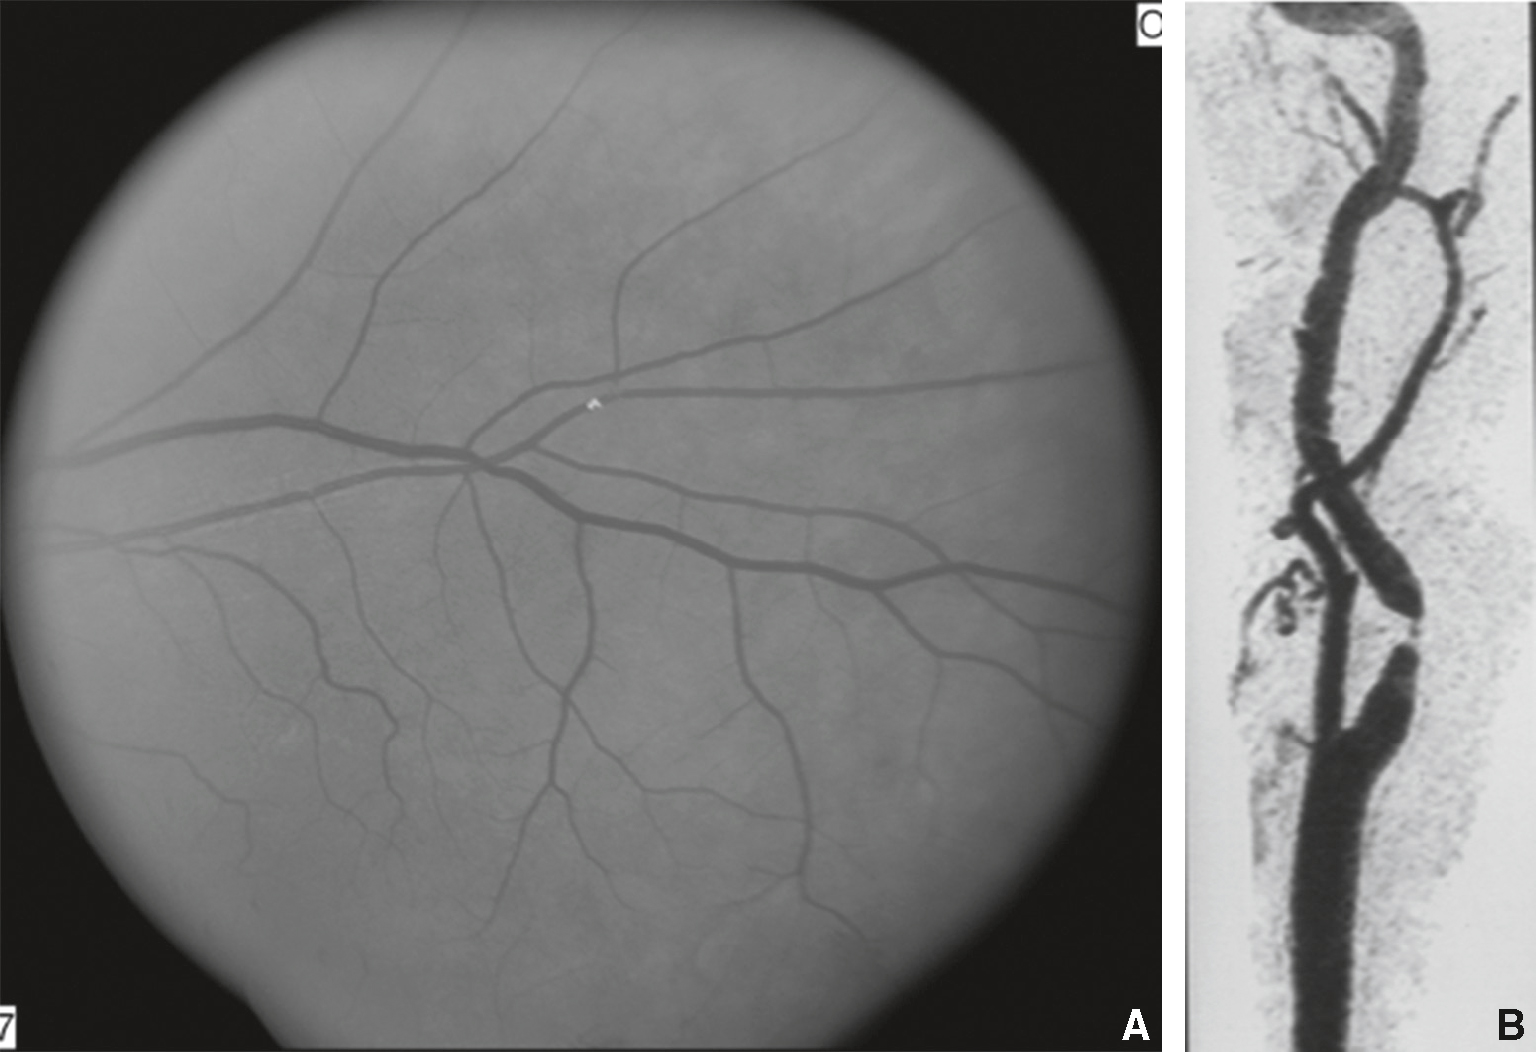

• Mécanisme : généralement embolique; la mise en évidence d’emboles de cholestérol au niveau des bifurcations artérielles à l’examen du fond d’œil est rare, mais pathognomo-nique (fig. 3.3).

Fig. 3.3

Cécité monoculaire transitoire d’origine embolique (amaurose fugace).

A. Embole de cholestérol visible au fond d’œil. B. Sténose athéromateuse serrée de l’artère carotide interne au cou en angioscanner.Image combinée illustrant une amaurose fugace, manifestation de cécité monoculaire transitoire d’origine embolique. La vue A correspond à une photographie du fond d’œil en angiographie, montrant le réseau vasculaire rétinien avec un flux interrompu au niveau d’une branche artérielle centrale, typique d’un embole obstruant temporairement la circulation. L’image B, en tomodensitométrie ou angioscanner, révèle une sténose significative ou une plaque athéromateuse ulcérée au niveau de l’artère carotide interne, probable source emboligène. Ce lien entre embolie carotidienne et ischémie rétinienne transitoire est essentiel pour évaluer le risque d’AVC et orienter la prise en charge en urgence.